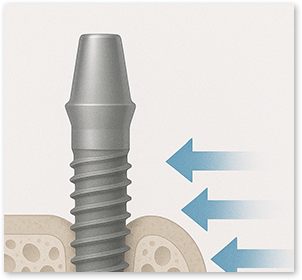

Improved Initial Stability

Improved bone-cell attachment helps secure implant stability

1.7x Higher Bone Integration

Compared with conventional implants, plasma implants showed about 1.7 times higher bone integration within 4 weeks. (Based on 4-week follow-up of actual patients)

94% Bone Integration in Just 4 Weeks

With faster osseointegration, a 94% bone integration rate was reported in a short period. (Based on a publication involving Harvard researchers)